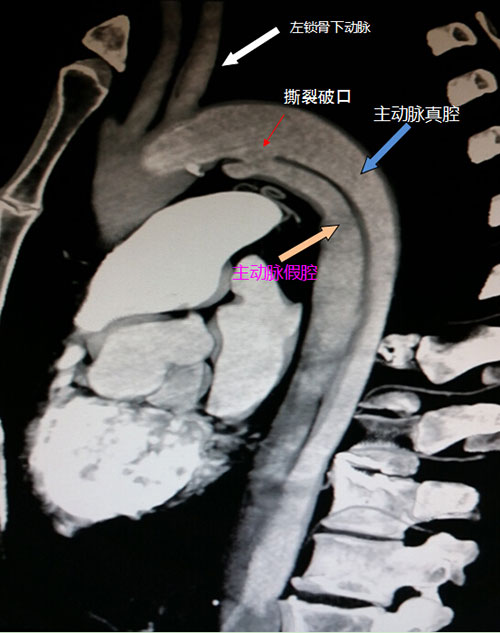

主动脉血管分内、中、外三层。主动脉夹层就是血流撕裂了内膜,在中膜层将完整的动脉壁分开,使得本来是一个管腔的主动脉变成了两个管腔,新撕开的管腔称为假腔,而原来就有的管腔称为真腔。主动脉承受直接来自心脏跳动的压力,血流量巨大,主动脉壁在发生撕裂后变得异常薄弱,如果不进行恰当和及时的治疗,很有可能在血流的持续高压冲击下突然破裂,如果主动脉夹层破裂,几乎是九死一生。

在影像学结果出来后,首诊医生马上请我院援疆专家何鹏程主任进行会诊,何鹏程主任认为患者Debakey Ⅲ型主动脉夹层诊断明确,假腔明显扩大,在积极药物治疗的基础上,需要实施主动脉腔内修复术。主动脉腔内修复术就是在主动脉内部植入带膜(通常为聚四氟乙稀,PTFE)的金属支架,利用缝合在金属骨架上的PTFE膜封闭主动脉破口,阻断从真腔流入假腔的血流,从而预防假腔进一步扩张,降低主动脉破裂风险,这有点类似日常生活中的补轮胎,只是过程要复杂、精细得多。

这例患者就属于这种情况,由于患者主动脉的破口紧邻左锁骨下动脉,从主动脉修复的角度必须把左锁骨下动脉完全覆盖才能保证把破口完全堵闭,而患者的左锁骨下动脉十分粗大,其所发出的负责左侧小脑供血的椎动脉也十分粗大,直径达到右侧椎动脉的两倍,这就意味着如果覆膜支架把左锁骨下动脉完全覆盖,将很有可能引起左锁骨下动脉供血的左上肢及左侧小脑缺血,可引发脑梗死甚至死亡等严重后果。